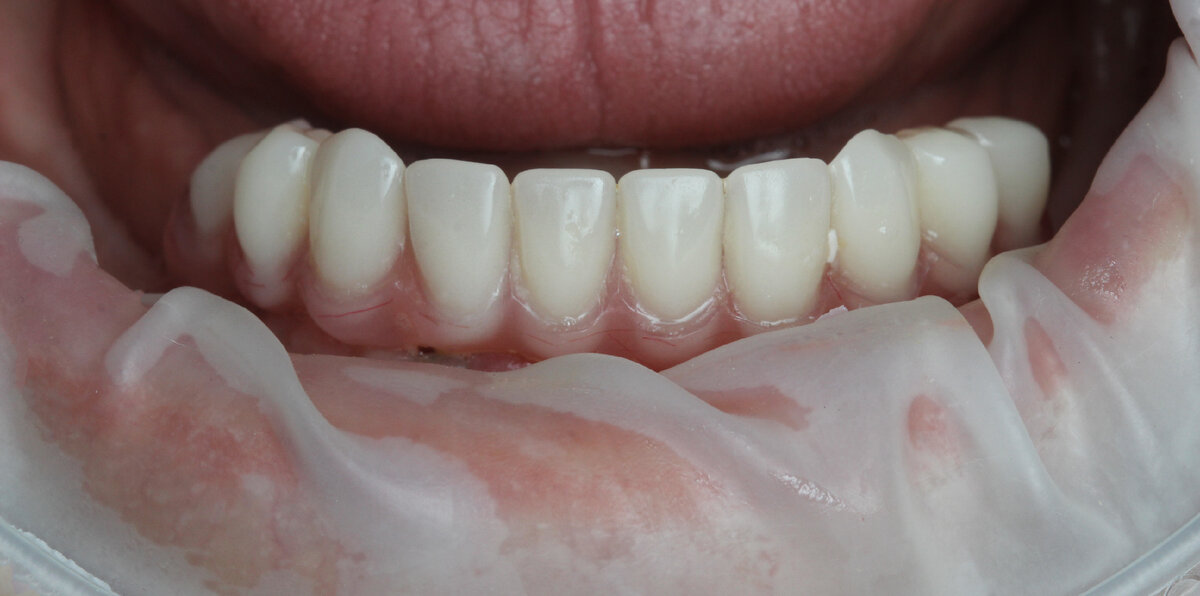

Готовый к фиксации в полости рта акрил-титановый протез нижней челюсти.